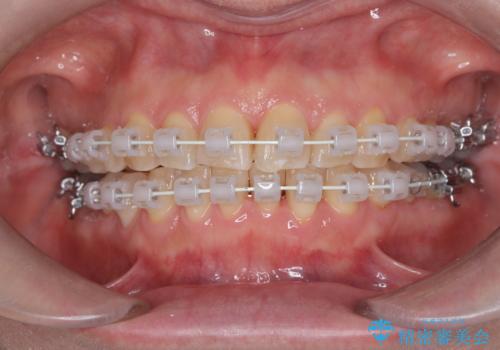

今回の矯正治療では、歯の色に近い目立たない審美ブラケットとワイヤーを使用しました。

スペース確保のために、まず奥歯全体をわずかに後方へ動かす遠心移動を実施し、前歯を並べるためのスペースを確保。さらに、安全性に配慮しながら歯の側面をわずかに削るIPRを併用し、デコボコを解消しました。